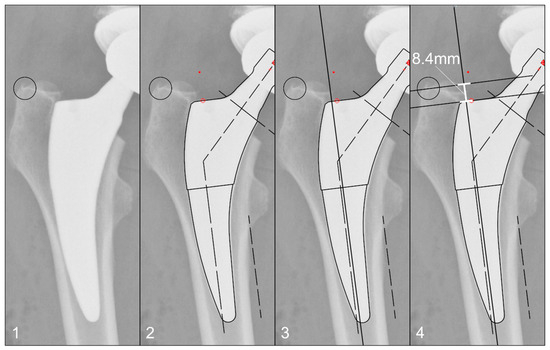

The radiographs were analysed with TraumaCad® software (Brainlab AG, Munich, Germany). We used only standardised deep-centered anteroposterior X-rays of the pelvis, with the central beam perpendicular to the midline and centered over the symphysis, and the legs positioned in 15° of internal rotation with the patient in the supine position. The images were calibrated by measuring the length of the depicted stem from its shoulder to its tip and equating it with the corresponding planning template. In this way, we could avoid any possible errors in our established calibration method with a reference sphere, which can be placed too far away from the central beam or too far away from the film. The measurements of the stem position were subsequently taken on the same axis to neutralise distortions caused by varying flexion and rotation positions of the leg during radiography (Figure 2). The varus/valgus alignment of the stems was determined by measuring the angle between the longitudinal axis of the stem and the longitudinal axis of the femoral canal (Figure 3). Subsidence was determined by measuring the distance from the shoulder of the stem to a clearly definable point at the greater trochanter in the previously determined longitudinal axis of the stem (Figure 4). Due to possible osseous changes over time, such as enthesiopathies or ossifications at the tip of the greater trochanter, defining this point was crucial to measure the correct distance.

Figure 3. Method for measuring the varus/valgus angle of the stem: (1) Initial image. (2) Calibration of the image using a planning template, as shown in Figure 2. (3) Determination of the femoral longitudinal axis. (4) Measuring the angle between the femoral longitudinal axis and the long axis of the stem according to the planning template.